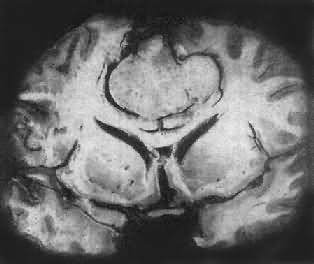

图16-23 星形胶质细胞瘤 左大脑半球肿胀,肿瘤边界不清,部分呈胶冻状 镜下,肿瘤细胞形态多样,可相似于纤维型星形胶质细胞、原浆型星形胶质细胞和肥胖星形胶质细胞,故分别称为纤维型、原浆型和肥胖型星形胶质细胞瘤。前二者为良性肿瘤,后者性质介于良恶性之间。如肿瘤细胞出现间变,细胞密度增大,异型性明显,核深染,出现核分裂像,毛细血管内皮细胞增生,则为间变性星形胶质细胞瘤,为恶性肿瘤。 高度恶性的星形胶质细胞瘤称为多形性胶质母细胞瘤(glioblastoma multiforme),多见于成人。肿瘤好发于额叶、颞叶白质,浸润范围广,常可穿过胼胝体到对侧,呈蝴蝶状生长(图16-24)。瘤体因常有出血坏死而呈红褐色。镜下,细胞密集,异型性明显,可见怪异的单核或多核瘤巨细胞。出血坏死明显,是其区别于间变性星形胶质细胞瘤的特征。毛细血管明显增生,内皮细胞增生、肿大,可导致管腔闭塞和血栓形成。肿瘤发展迅速,预后极差,患者多在2年内死亡。

图16-24 多形性胶质母细胞瘤 发生于儿童、青少年的毛发细胞型星形胶质细胞瘤,生长极为缓慢。有报道称患者在不完全切除肿瘤后有带瘤存活达40年者。该瘤常位于小脑、第四脑室底部、第三脑室、丘脑和视神经。其形态特点是由双极性的肿瘤细胞两端发出纤细的毛发状突起。即使有毛细血管增生,本瘤的预后仍相对较好。 应该指出,同一肿瘤的不同区域,瘤细胞可有不同的形态特征,且分化程度也不尽相同,因此肿瘤的分型仅具有相对的意义。 星形胶质细胞瘤的细胞骨架含有胶质纤维酸性蛋白(GFAP),免疫组织化学染色呈阳性反应,是该肿瘤的特异标志。 2.少突胶质细胞瘤(oligodendroglioma) 约占颅内胶质瘤的5%,主要见于30~40岁的成人,男女发病的机会相等。本瘤绝大部分位于大脑半球皮质的浅层,尤以左额叶为多见。 肉眼观,肿瘤呈灰红色边界清楚的球形肿块,位于白质和邻近的皮质,并可累及软脑膜。囊性变、出血和钙化颇为常见,其中钙化灶对X线诊断有一定帮助。 镜下,瘤细胞大小均匀,形态单一,弥漫排列,胞核居中着色深,胞浆空,环绕胞核形成空晕。间质富有血管,有不同程度的内皮细胞增生。约有20%病例可出现瘤细胞钙化,其范围大小不一,其中7%为镜下钙化,有时钙化灶较大,可在X线片上显示出来。如肿瘤组织中混有星形胶质细胞瘤成分达到50%,则称混合性少突星形胶质细胞瘤。 本瘤生长缓慢,病程可长达10~30年,临床表现多为癫痫和局部性瘫痪。少数生长迅速,酷似多形性胶质母细胞瘤,预后不佳。 3.室管膜(细胞)瘤(ependymoma)起源于室管膜细胞,患者多为儿童和青少年。本瘤占颅内胶质瘤的5%~6%,多见于第四脑室,其次为侧脑室、第三脑室和导水管。脊髓病变多发生于腰胝及马尾部。 肉眼观,颅内室管膜瘤呈膨胀性生长,边界清楚,呈球形、分叶状或乳头状,肿瘤多在脑室内生长。切面灰白色,呈均匀或颗粒状,可发生灶性出血甚至坏死或囊性变,有时也可发现点状钙化。 镜下,瘤细胞大小形态一致,呈梭形或胡萝卜形,胞核圆或椭圆,染色质呈细颗粒状,核膜清楚,有核仁。瘤细胞胞浆丰富,突起明显。瘤细胞的排列有二种特征,一是环绕空腔排列成腺管状,形态上与室管膜腔相似,称为菊形团形成,另一是环绕血管形成假菊形团结构,瘤细胞有细长的胞浆突起与血管壁相连(图16-25)。细胞中有神经胶质纤维,以PTAH染色在个别细胞的腔面或胞核旁可见纤毛体,后者与纤毛运动有关,是室管膜细胞的特征性结构。此外,有时还可形成乳头状结构。发生在脊髓圆锥和终丝的肿瘤,乳头状结构轴心中的结缔组织往往富含粘液。